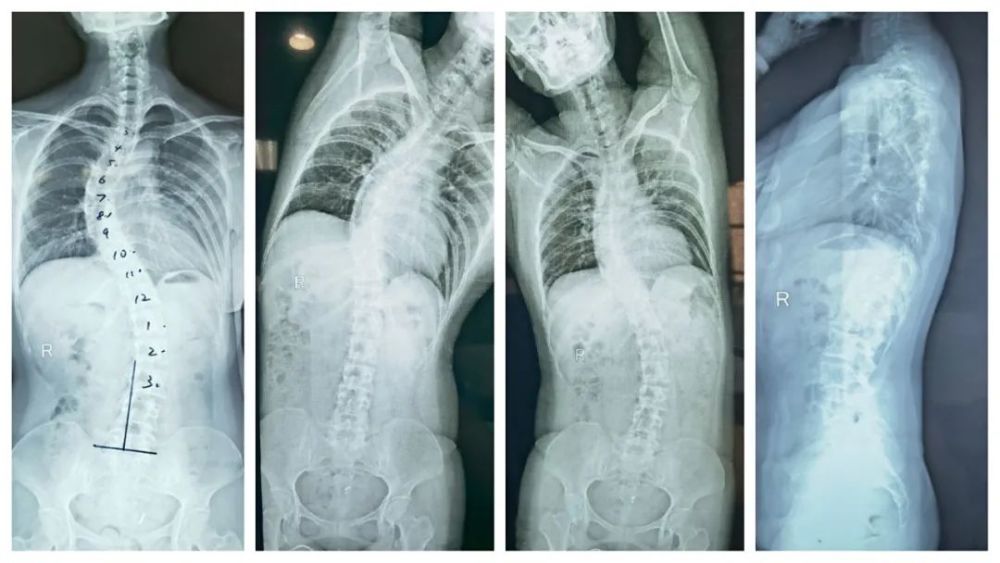

脊柱侧弯四十度图片,脊柱侧弯图片严重图片

病例分享成人脊柱侧弯畸形一例

女孩脊柱侧弯50度治疗半年后减至38度成功避免手术